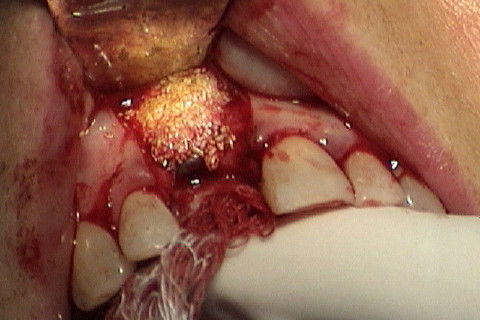

Enxerto com tecido ósseo xenogeno

Paciente com fratura do elemento 11. Como havia grande perda óssea vestibular, optamos por fazer implante primeiramente a extração do dente e após 4 meses a colocação do implante. Concomitante 'a colocação do implante, enxerto óssseo + membrana para regeneração óssea foi colocado e aguardamos 6 meses para então fazermos a reabilitação com coroa metalo-ceramica parafusada.